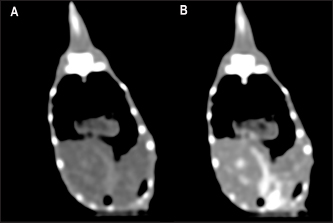

Fig. 3. The postcontrast CT transverse images displayed in the soft tissue window show better contrast enhancement in the hepatic section observed at 60 seconds (B) than at 30 seconds (A) after contrast administration.

The contrast study was successfully performed in 27 out of 30 animals (15 veiled chameleons and 12 panther chameleons). However, accidental contrast extravasation occurred in three veiled chameleons and two panther chameleons, with contrast remaining adjacent to the injection site tissue. In the postcontrast study, the contrast enhancement was better observed at 1 minute than 30 seconds after contrast administration (Fig. 3). Therefore, 1-minute postcontrast images were used for the postcontrast attenuation measurements.